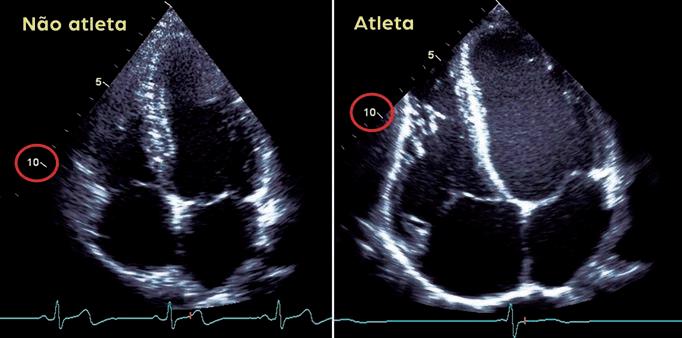

Quando as pessoas excedem estas diretrizes, o coração pode remodelar-se em resposta – isto é, começa a mudar o seu tamanho e forma. Como resultado, a função cardíaca também pode mudar. Essas mudanças na estrutura e função do coração entre pessoas que praticam altos níveis de exercícios são chamadas de coração de atleta ou coração de atleta. O coração atlético não causa necessariamente problemas, mas em algumas pessoas pode aumentar o risco de certos problemas cardíacos.

Entre os corredores, por exemplo, o coração se remodela em resposta à necessidade de bombear um grande volume de sangue. Como resultado, as câmaras do coração aumentam para reter e bombear mais sangue. Entre os levantadores de peso, o coração se remodela, engrossando em resposta ao aumento da pressão aplicada sobre o coração.